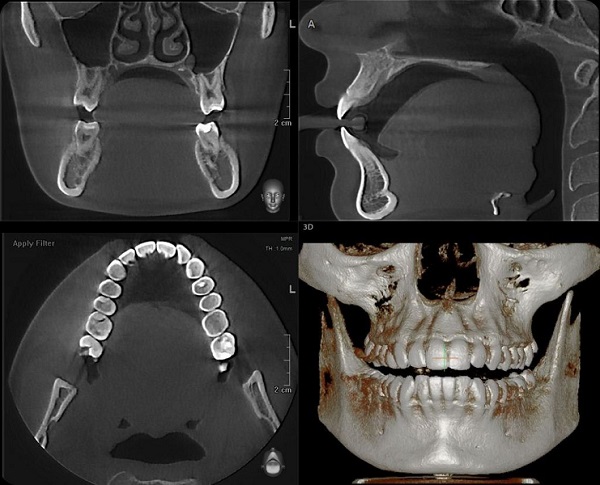

Курс ориентирован на широкую аудиторию: студенты стоматологических факультетов 3-5 курсов, клинические ординаторы, аспиранты, практикующие врачи-стоматологи, врачи-оториноларингологи. МООК направлен на теоретическую подготовку обучающихся и практикующих врачей к работе с 3д рентгенологическим исследованием-КЛКТ. Курс помимо теоретической базы содержит включение практико-ориентированных иллюстративных заданий, направленных на тренировку практической работы. В задачи курса входит полное ознакомление с неограниченными возможностями КЛКТ для диагностики патологий челюстно-лицевой области.